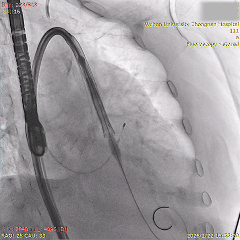

术中影像

瓣膜初始负位定位

第一次瓣膜释放,可见瓣膜轻微向下移动